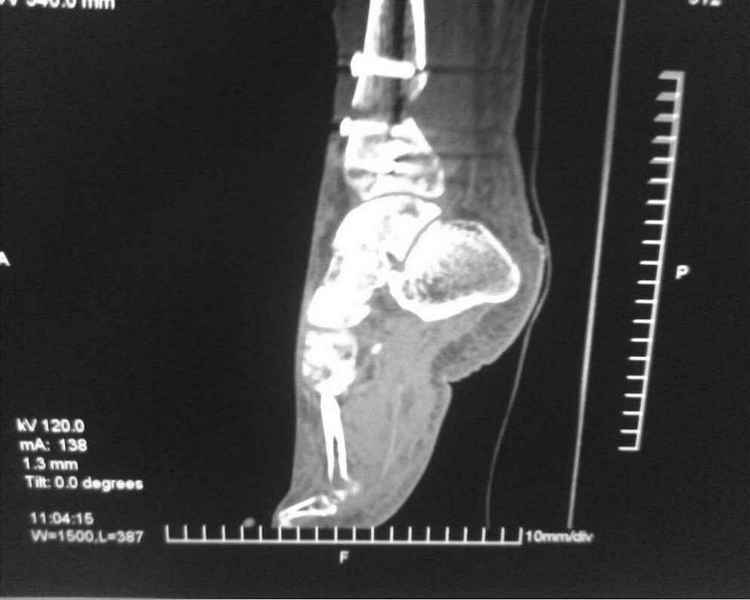

[Ortho] [1/2] Метатарзал краш синдром в порочном сращении (эквинусная стопа), несращение сегментарного перелома костей голени после БИОС , ПТФБ, ХВН СЕАР С-6.

Больной 39 лет. Травма получена в ДТП 21.09.09г. был госпитализирован в обл. больницу

соседней области с диагнозом сочетанная травма зчмт сотрясение головного мозга

сегментарный перелом костей правой голени с\3-н\3, суральный флеботромбоз циркулярные

некрозы н\3 правой голени правого голеностопного сустава лечение скелетным вытяжением за

пяточную кость. переведён в наше отделение 6.10.09г. возобновлено скелетное вытяжение,

перевязки, иссечение некрозов, антикоагулянты. На уздг диагноз флеботромбоза

подтвержден. 28.10.09 операция БИОС правой б\берцовой кости штифтом PTNL остеомед .

остеосинтез м\берцовой кости не выполняли из-за наличия гранулирующих ран и некрозов в

месте операционного доступа. Вторым этапом планировалось наложить аппарат Илизарова для

выведения стопы из эквинуса и динамизации штифта. Но из-за наличия гранулирующих ран и

некрозов в местах проведения спиц на стопе и голени 19.11.09 переведен в ожоговое отделение

для САДП гранулирующих ран после некрозов. 23.11.09 САДП. В послеоперационном периоде-

длительное заживление ран с лизисом кожных лоскутов, манифестное развитие ХВН с

формированием трофических язв и лимфэдемы. Больной явился на госпитализацию 13.01.10г.

локальный статус и свежие снимки прилагаю. Данные уздг выложу позже. Что в этой ситуации

делать я не знаю. Признаков сращения на Rg-нет плюс метафизарный фрагмент кивнул на вальгус.